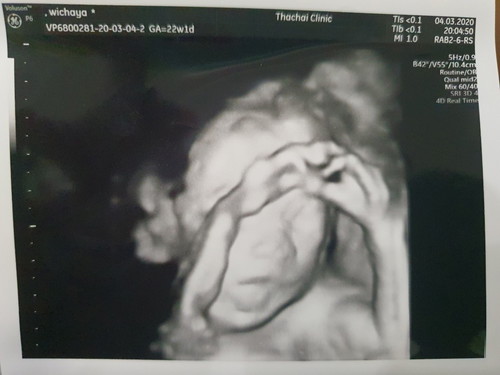

ซาว 4 D 22 weeks

สงสัยอยากเป็นนักมวย

ตั้งการ์ดมาเลยลูกกกก

ท่าได้มากเลยค่ะ 5555